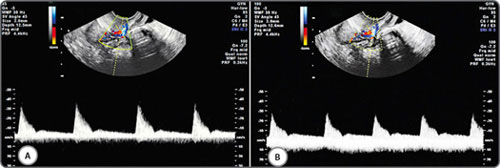

Figs 14A and B: Wall motion filter (pulse wave Doppler): A higher filter setting (A) can affect pulse wave forms in comparison with optimal setting (B)

Figs 15A and B: Doppler sample volume (Doppler gate) size and location: The width of the Doppler gate is kept 2 mm (A) and 3 mm (B). In figure (B), the Doppler gate is wider than the diameter of the artery and is placed partly over an adjascent vein and therefore picking up both arterial and venous flow

It follows therefore that too small a sample box placed centrally over a vessel may over-estimate the true flow. Whilst the diameter of the ascending uterine artery ranges from 2 to 5 mm in the non-pregnant patient, the spiral arteries at the level of the endometrium measure 1 to 2 mm in diameter. The diameter of the ovarian stromal vessels are also around 1 to 2 mm. This leaves little room for placement error considering 9the smallest volume box usually starting at 1 mm. The width of the volume box (Doppler gate) should be adjusted to the inner diameter of the vessels to be evaluated.